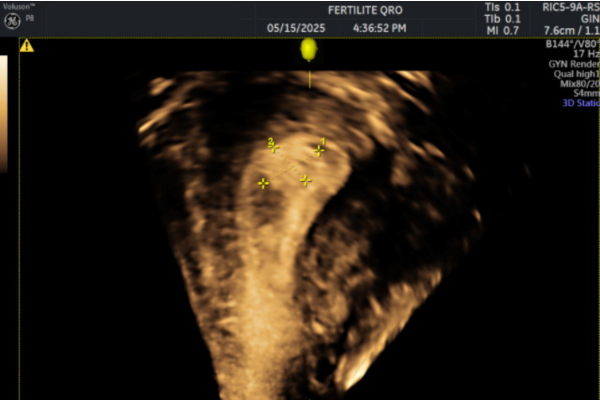

- Ecografía transvaginal:

Es el primer estudio recomendado. Permite observar engrosamientos o imágenes compatibles con pólipos dentro del endometrio. Es rápida, accesible y no invasiva.

Imágenes de pólipos endometriales